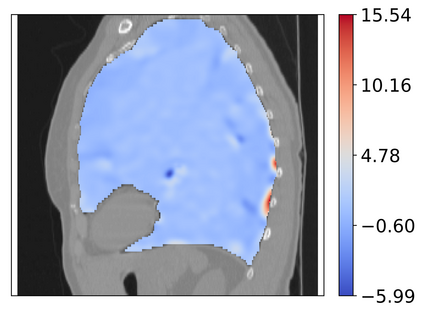

Deformable image registration is a fundamental task in medical image analysis and plays a crucial role in a wide range of clinical applications. Recently, deep learning-based approaches have been widely studied for deformable medical image registration and achieved promising results. However, existing deep learning image registration techniques do not theoretically guarantee topology-preserving transformations. This is a key property to preserve anatomical structures and achieve plausible transformations that can be used in real clinical settings. We propose a novel framework for deformable image registration. Firstly, we introduce a novel regulariser based on conformal-invariant properties in a nonlinear elasticity setting. Our regulariser enforces the deformation field to be smooth, invertible and orientation-preserving. More importantly, we strictly guarantee topology preservation yielding to a clinical meaningful registration. Secondly, we boost the performance of our regulariser through coordinate MLPs, where one can view the to-be-registered images as continuously differentiable entities. We demonstrate, through numerical and visual experiments, that our framework is able to outperform current techniques for image registration.